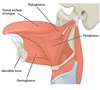

Suprahyoid musucles

- digastric

- geniohyoid

- stylohyoid

- mylohyoid

Digastric

ACTION: depress mandible; elevates hyoid during swallowing

ATTACHMENT: Anterior and posterior bellies, from the digastric fossa of the mandible and the mastoid notch of the temporal bone to the intermediate tendon to body and greater horn of hyoid bone

INNERVATION: CN V/anterior belly,CN VII/posterior belly

**suprahyoid ms**

Geniohyoid

ACTION: depress mandible; elevates hyoid

ATTACHMENT: from the inferior mental spine of the mandible to the body of the hyoid

INNERVATION: C1 via CN XII

**suprahyoid ms**

Stylohyoid

ACTION: draws hyoid posteriorly & elevates it

ATTACHMENT: superior to post belly digastric, from the styloid process of the temporal bone to the body of they hyoid, superior!!!

INNERVATION: CN VII

**suprahyoid ms**

Mylohyoid

ACTION: elevates hyoid and floor of mouth

ATTACHMENT: mylohyoid line of the mandible and the mylohyoid raphe on the body of the hyoid one. , makes up floor of mouth

INNERVATION: CN V3 = mandibular br. of trigeminal n.

**suprahyoid ms*